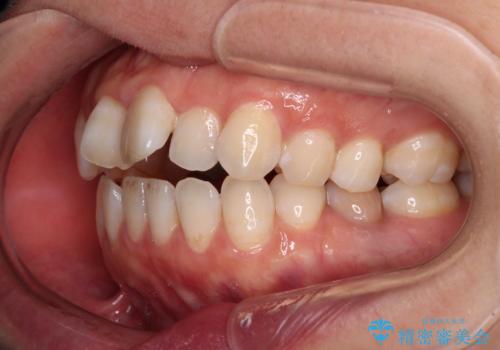

【モニター】飛び出した上顎前歯 補助装置を併用したインビザライン矯正治療

- 上下前歯が非接触となり、前方に突出していることを気にして来院された患者様です。

上下の前後差が大きいため、インビザライン単独での上顎歯列移動は困難と判断し、補助装置により上顎歯列を後方移動させ、その後インビザラインにて仕上げていくこととしました。

また、舌の突出癖が非接触の原因の大きな要因と考えられるため、舌のトレーニングをしっかり行っていくよう指導しました。